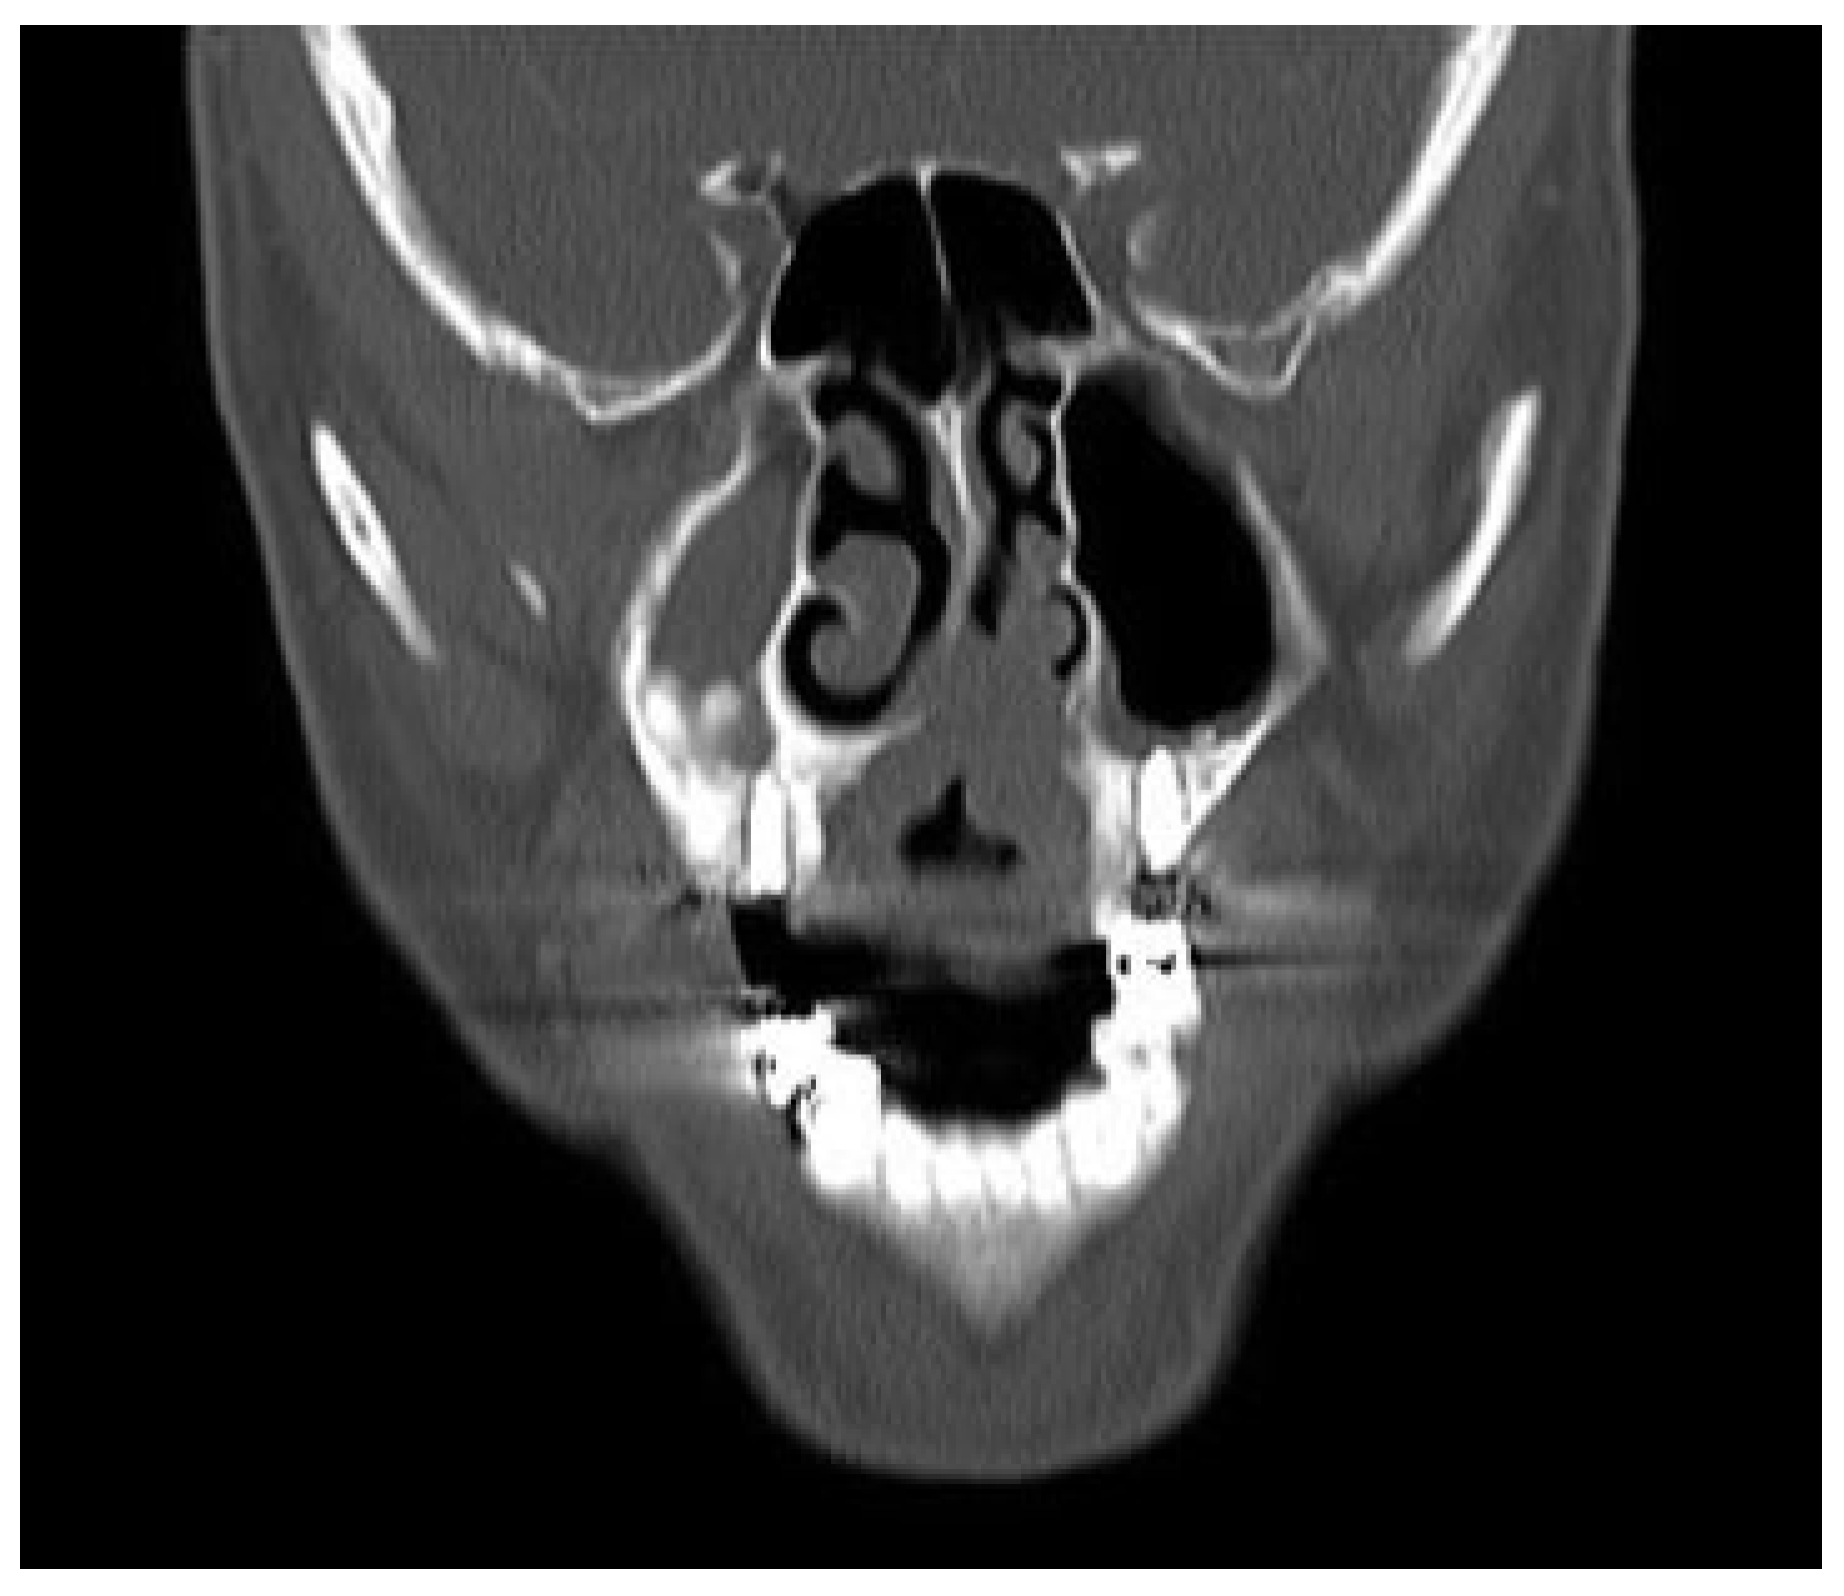

Figure 2. Preoperative CT showing the intranasal extension of the tumor.

Once in the operating room, the kind of intubation should be individualized. For unilateral tumors, intranasal intubation is preferred to improve the intraoral visualization and facility tumor resection. Submental intubation represents an effective alternative especially with tumors affecting both nostrils. This technique places the endotracheal tube away from our surgical field and improves the tumor visualization. In the surgical technique, first, a free margin is delimitated on the palatine mucosa reaching the bone layer and a palatine osteotomy is done using an oscillating saw (Figure 1). Next, a vestibular maxillary approach is done and microplates are fixed at both sides of the maxilla to guarantee the correct reposition of the maxilla at the end of the procedure. Screws and microplates are removed and a Le Fort I osteotomy is performed. This represent the most critical point of the approach and attention must be directed to the piriform aperture, lateral nasal walls, and the septum in order to make the cuts without entering into the tumor. Preoperative imaging is crucial to determine the intranasal extension of the tumor and decide the level of the Le Fort osteotomy (Figure 2). Vertical extension of the tumor determines the most limiting factor and tumors with high intranasal extension may not be candidates for this kind of approach, as the risk of tumor disruption is higher in these cases.